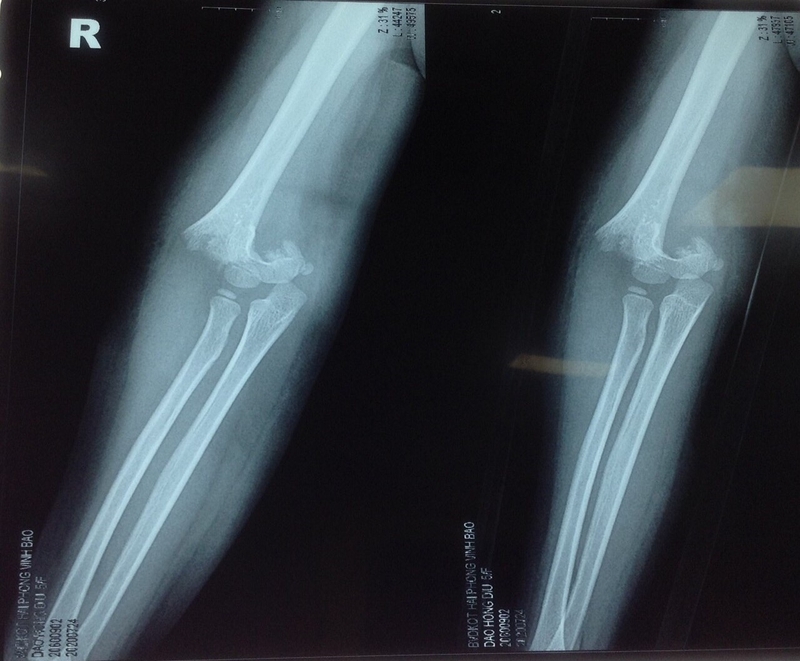

Phương pháp X-quang hỗ trợ chẩn đoán gãy trên lồi cầu xương

Hiện nay, cách chẩn đoán gãy trên lồi cầu xương cánh tay hiệu quả và được dùng nhiều nhất là tiến hành chụp X-quang để nhận diện tình trạng xương khớp rõ ràng, từ đó quan sát mức độ gãy xương và chỉ định điều trị cho phù hợp, an toàn, hiệu quả.